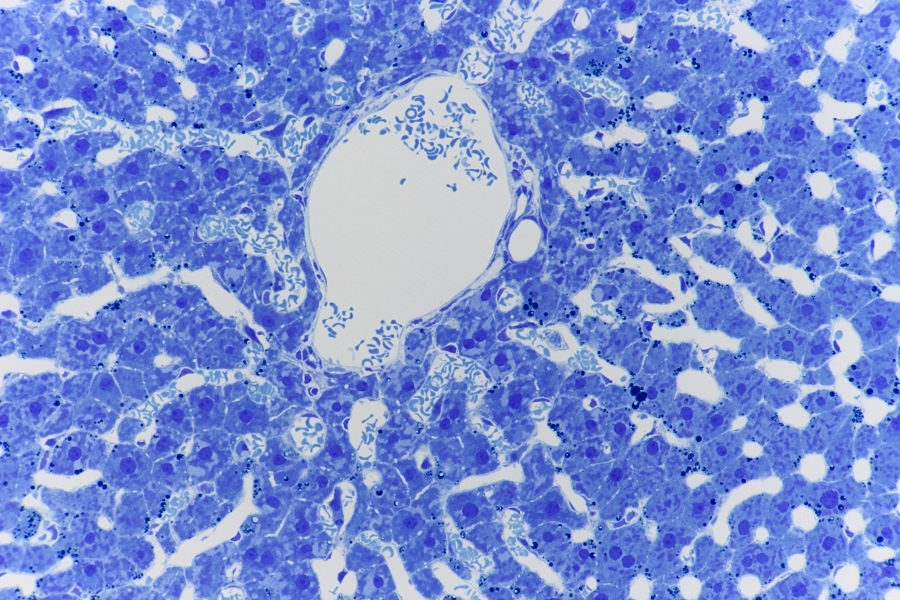

Bild3,

Übersicht Bild. Objektiv Leitz plan Fluotar 4x.

Objektiv Leitz plan Fluotar 25x.

Bild6,

Objektiv Leitz plan apo 63x na 1.4.

Zitat Sobotta, Seite 396-397

Die Wand der Sinusoide wird von dünnen Endothelzellen gebildet, deren Zytoplasma von Feldern mit unterschiedlich großen offenen Poren durchsetzt wird.

Ein weiterer Zelltyp ist Teil der Wand der Sinuoide, die von-Kupffer-Sternzellen (Kupffer-Zellen = Leber-makrophagen).  Sie sind reich an Lysosomen und Phagozytieren intensiv Partikel und Mikroorganismen, die über das Blut in das Leberläppchen gelangen. Bei Verlust der Milz übernehmen die Kupffer-Zellen weitgehend den Abbau der gealterten Erythrozyten. Die Kupffer-Zellen liegen dem Endothel auf, durchsetzen es aber mit einzelnen Fortsätzen. Ein Teil der Fortsätze erstreckt sich weit in das Lumen der Sinusoide, zum Teil bis zur gegenüberliegenden Wand; das hilft ihnen, Partikel abzufangen.

* = Sinusoide (meist Leer weil mit Perfusion die meisten Blutzellen weggespült werden);

A = Zellkern von-Kupfferzelle;

B = Ein Fortsatz mit abgefangen Partikel;

C = Endothelzelle;

D = Fett Tropfen die Sekundäre Osmium Fixierung enthalten bleiben;

E = Gallenkanälchen;

F = Rundliche, helle Zellkern der Hepatozyten.